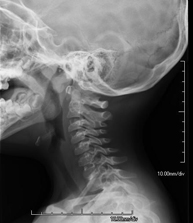

- RX Columna cervical

Tècnica que usa els raigs X a través de la qual s'obtenen imatges de la columna cervical per al seu estudi. Indicacions: traumatisme, dolor cervical. - RX Columna dorsal